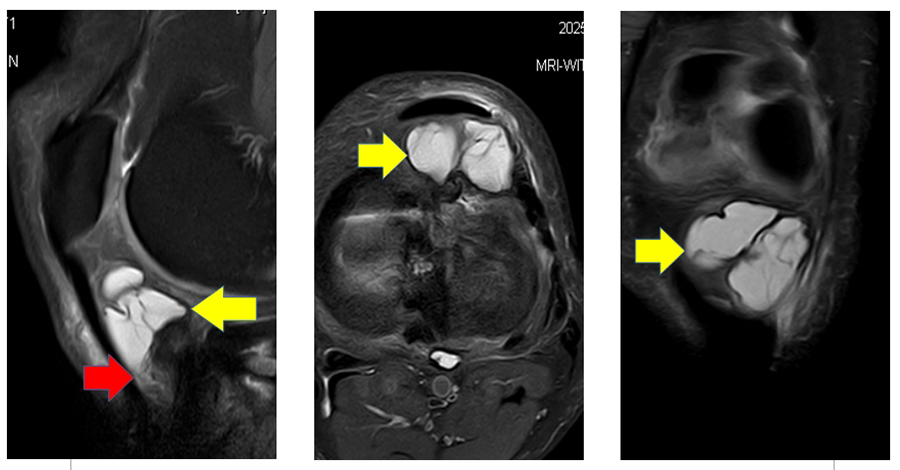

一位40歲女性因左膝疼痛及摸到腫塊求診骨科門診,初步X光檢查並無明顯異常發現。進一步磁振造影檢查則發現左側膝蓋於髕骨下方、髕骨韌帶後方的脂肪墊內有一群囊腫樣病灶聚集並且造成周邊組織水腫,其他膝蓋重要韌帶、肌腱及半月板等結構沒有明顯異常發現,也沒有關節腔積水。依照影像發現及臨床症狀判定為因腱鞘囊腫引起的髕骨下脂肪墊症候群。(如圖 A)

圖 A 左膝 髕骨下方脂肪墊內有一群囊腫樣病灶聚集(黃色箭頭)造成周邊組織水腫(紅色箭頭)